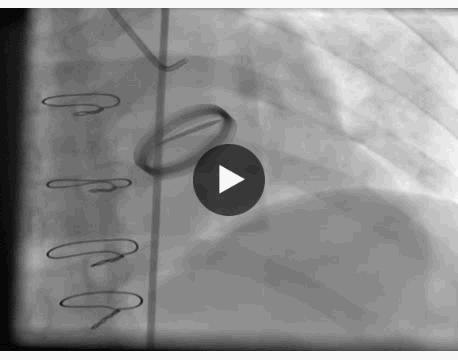

冠脉造影显示:左主干未见明显异常,前降支近中段动脉硬化,未见明显狭窄及血栓,远端血流TIMI 3级,回旋支全程可见散在斑块,近段局限性狭窄约50%,远段血栓影消失,远端前向血流TIMI 3级。

右冠脉动脉硬化,近中段可见多处局限性斑块病变轻度狭窄,远端血流TIMI 3级。 结论:符合冠心病、急性心肌梗死改变,目前回旋支远段血栓自溶,未见明显狭窄病变,暂不予以支架植入。

主要造影结果

为避免冠脉介入治疗过程中大剂量抗凝药物的使用导致月经量进一步增加及凝血功能状态严重异常,故未在月经期间予以支架植入,仅在华法林基础上联合抗血小板治疗,并密切观察,拟月经期结束后择期冠脉介入治疗。观察期间,患者未出现胸闷、胸痛等症状。

月经期结束后复查冠脉造影显示,回旋支远段血栓影消失,远端前向血流TIMI 3级。

回旋支远段血栓自溶,考虑为抗凝、抗血小板作用及患者月经期凝血状态、雌激素水平改变共同影响。处于月经期女性发生急性心肌梗死,若病情平稳应如何处理,目前指南并没有明确推荐。